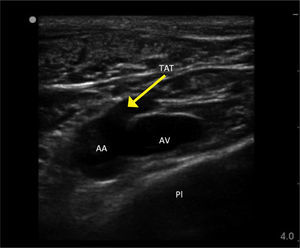

Guía con ultrasonidoLa clavícula bloquea las ondas de ultrasonido por lo que se requiere una aproximación más lateral, ya sea supra o infraclavicular12. Estudios recientes han demostrado beneficios con el uso de ultrasonido por esta vía13,14. El uso de ecografía permite evitar la pleura, la arteria axilar (y las ramas del tronco tóracoacromial que pasan por anterior de la vena), la vena cefálica y el plexo braquial (Figura 2). En pacientes obesos o con importante masa muscular, la vena puede ser difícil de visualizar con ultrasonido.